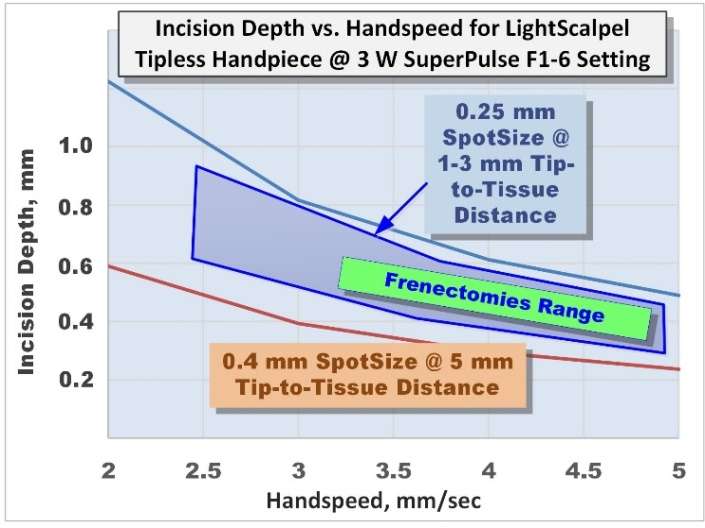

Just like the sharpness of the steel blade defines the quality and ease of the incision, the size of the laser beam focal spot determines the quality of the laser cut. The smaller (or sharper) the focal spot of the beam, the narrower and deeper the incision. Just like a dull blade cannot produce a quality incision, an oversized laser beam spot cannot produce a precise and narrow incision. For cutting, the LightScalpel laser handpiece is maintained 1-3 mm away from the tissue and is moved at a hand speed of a few millimeters per second — as illustrated in Figure 6. For a rapid switch from cutting to just photo-coagulation, the laser beam can be defocused. Defocusing can be achieved either by selecting a larger spot size, or by simply moving the handpiece away from the tissue (by approximately 8 mm for LightScalpel tipless laser handpieces), and “painting” the “bleeder” for enhanced hemostasis (Figure 6).

For a laser scalpel, the power density of the focused laser beam is equivalent to the mechanical pressure that is applied to a cold steel blade. In other words, greater laser fluence[29] (i.e., greater power density and slower hand speed) results in greater depth and rate of soft tissue removal. During each SuperPulse pulse, the ablation depth δ is given by the formula δ = A (E – Eth) / Eth for the steady state ablation conditions,[30] where A is the absorption depth from Figure 4 and Eth is the ablation threshold fluence,[29] and E is the fluence during the SuperPulse pulse. At the 10.6 micrometers wavelength of the CO2 laser, the ablation threshold for a water-rich soft tissue with an assumed water content of 75% equals approximately Eth = 3 J/cm2. For repetitive pulses that are scanned across the soft tissue, the fluence is defined by the pulse frequency and the hand speed: i.e., the depth of incision depends on laser power settings, spot size, and the surgeon’s hand speed[33,34] (Figure 7).

A horizontal CO2 laser incision was made along the mucogingival junction (or the line where the tension is most apparent) following the contours of the underlying bone. The tip of the laser handpiece was held perpendicular to the target tissue at a distance of 1 mm–2 mm from it. The handpiece was moved at the recommended speed of 4-5 mm/second. While making the laser incision, the clinician feels the release of the tissue tension. If the created incision, however, does not provide satisfactory tension relief, additional passes may be needed. Typically, between 4 and 8 laser passes are made to achieve the desired depth of incision, and the procedure usually takes under 1 minute.